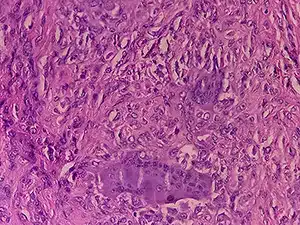

Tenosynovial giant cell tumor, seen here under a microscope, can now be treated with the CSF1 receptor inhibitor vimseltinib.